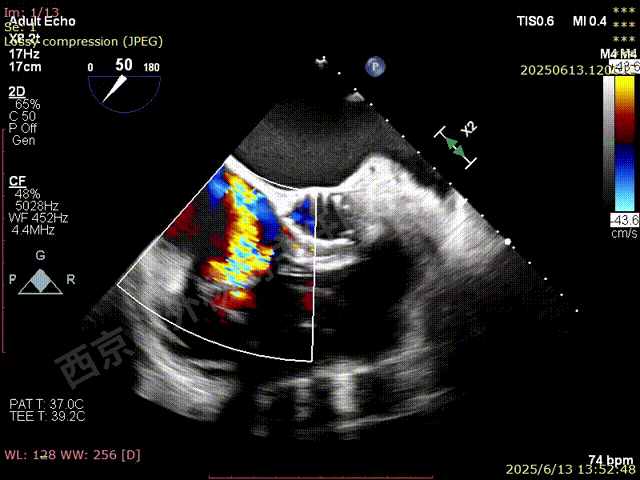

第一枚XTW释放后评估,外侧反流基本消失,内侧仍然有中度以上反流

第二枚XT关闭后评估,trace

二尖瓣平均跨瓣压差1mmHg

释放后评估,反流降至1+,组织桥稳定

M-TEER术后三尖瓣反流减轻